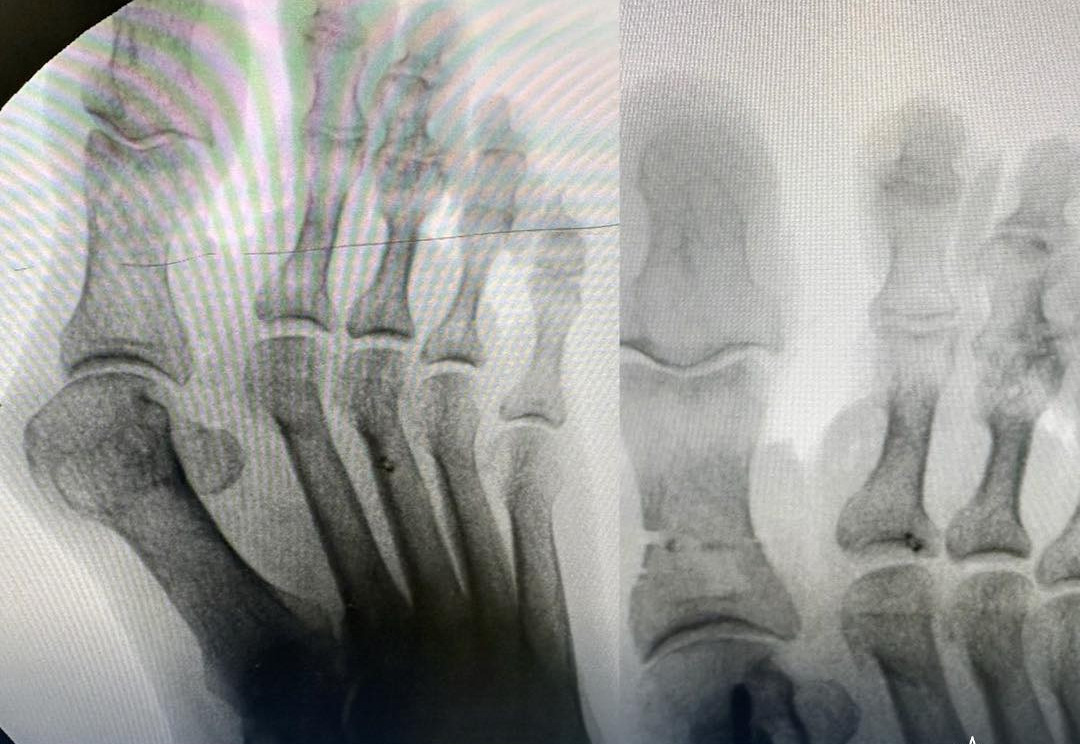

В Атырауской областной больнице успешно внедрён новый современный метод лечения вальгусной деформации первого пальца стопы — hallux valgus, сообщает AtyrauPress.